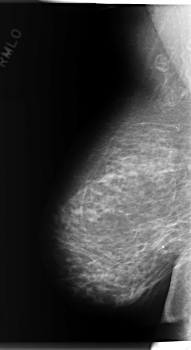

C_0280_1.RIGHT_MLO

RIGHT_MLO LINES 5944 PIXELS_PER_LINE 3240 BITS_PER_PIXEL 12 RESOLUTION 50 NON_OVERLAY